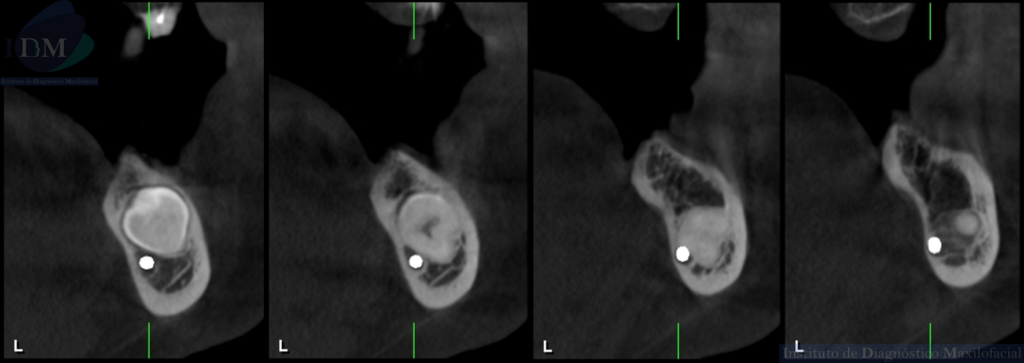

CORTES TRANSAXIALES

Siendo así que en la tomografía volumétrica de haz cónico se evidencia una hipercementosis radicular, con los segmentos radiculares contactando con el conducto dentario inferior. Finalmente se evidencia un borramiento del espacio del ligamento periodontal compatible con anquilosis dentaria.

A la evaluación de la radiografía panorámica se evidencia reabsorción ósea alveolar bimaxilar, edéntulo parcial bimaxilar y presencia de múltiples implantes con prótesis sobre implantes así como tratamientos restaurativos. Siendo lo más destacado una molar retenida en cuerpo mandibular izquierdo, la cual esta mesioangulada.